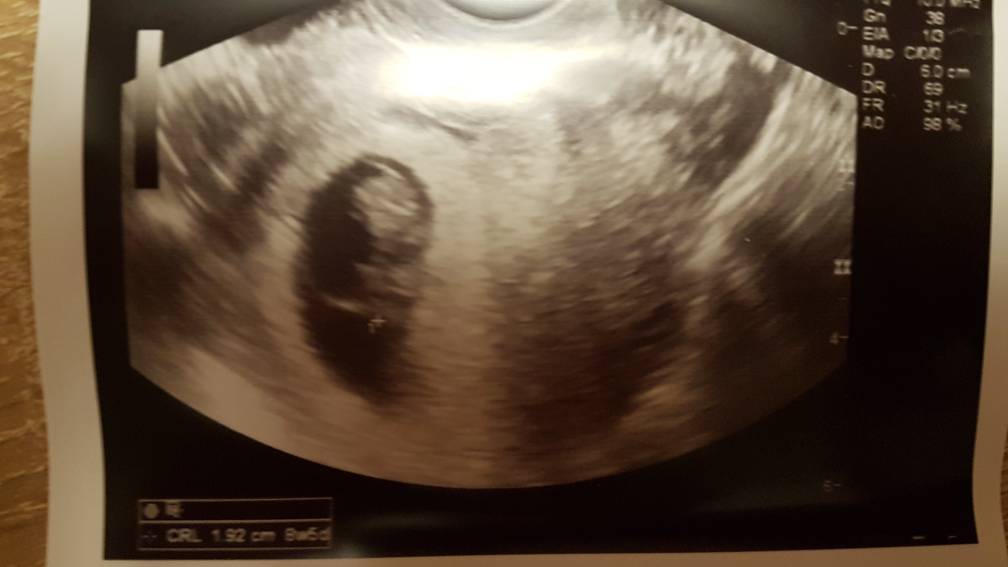

Zdaje relacje z wizyty , kropek mierzy prawie 2cm :) Według usg 8t5d... I chyba nadrobil ten tydzień i jest teraz na równo z usg i z OM... albo nie wiem [emoji23]

20190201_202055.jpeg

Według mojej ginekolog termin porodu 08.09 , a według lekarza na NFZ 15.09 [emoji848] KOGO SLUCHAC????[emoji848]Zobacz załącznik 939149